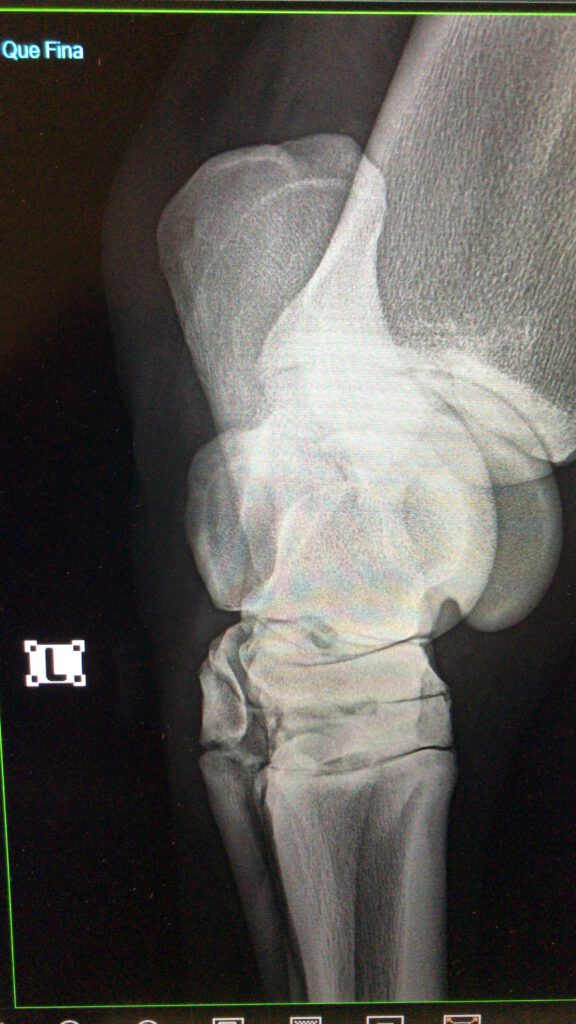

Orthopädie

Bildgebende Verfahren:

Ultraschall, Röntgen, JETZT auch Endoskopie